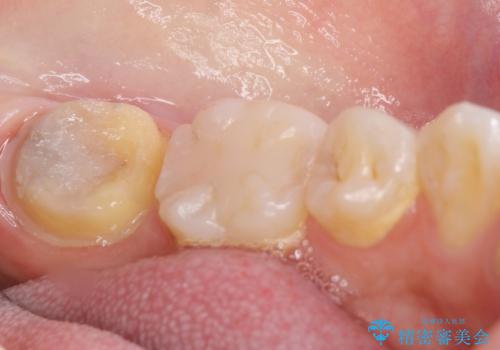

- 奥歯が黒くなっていることを気にされ来院された患者様です。

精査したところ、左下の奥歯にう蝕を認めました。

患者様のご希望により、う蝕を丁寧に除去したのちセラミッククラウンによる補綴治療を行いました。

セラミッククラウンの自然な仕上がりと咬み心地にご満足頂けました。

クラウンの種類:オールセラミッククラウン スタンダード